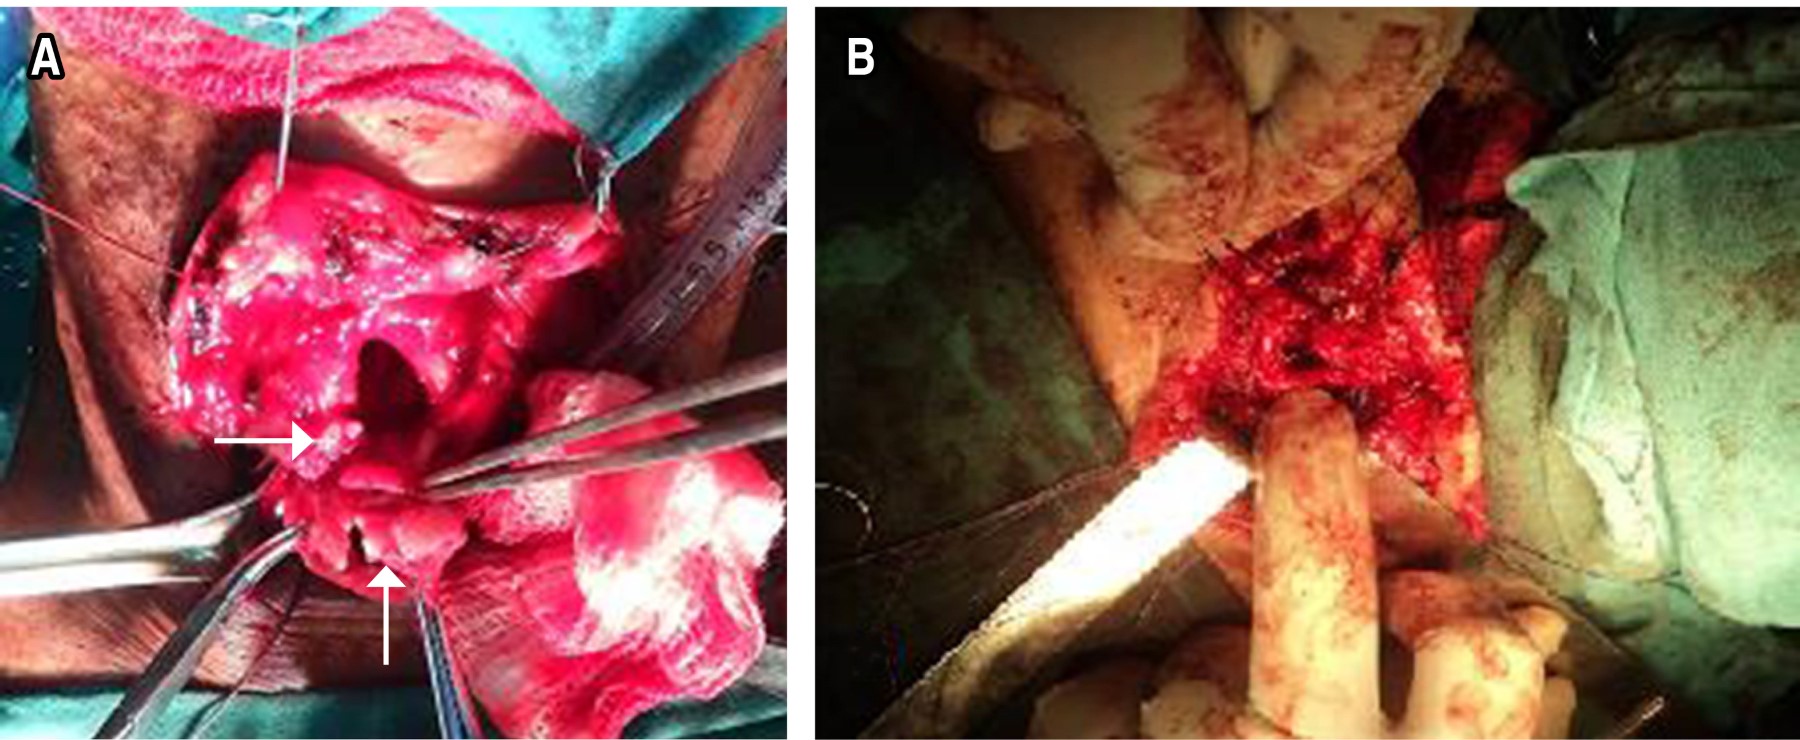

En todos se practicó resección laringotraqueal subglótica por la técnica de Pearson (Figura 2). Un paciente tenía parálisis recurrencial bilateral, por lo que en primera instancia se le realizó una cordoaritenoidectomía posterior y después la resección laringotraqueal. Sólo hubo una complicación, granuloma de la línea de sutura en el paciente previamente operado. Con un seguimiento de 18, 24 y 62 meses, dos enfermos tuvieron resultados satisfactorios, debido a debilidad de la voz, y uno excelente.